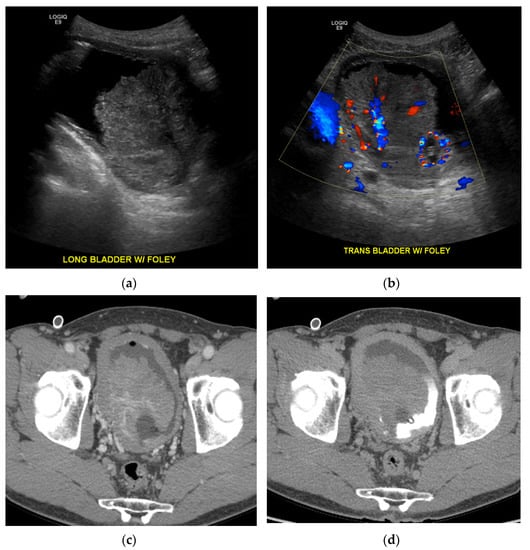

5.4. Ultrasound